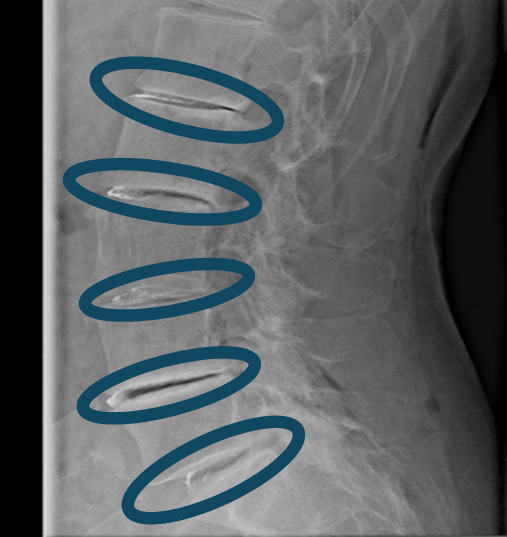

患者様と相談の元、 L1/2、2/3、3/4、4/5、5/S にセルゲル法を施行

DiscoGelを入れた後の画像になります。